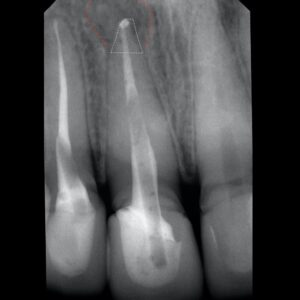

Апикальная хирургия — инновационный подход в современной стоматологии